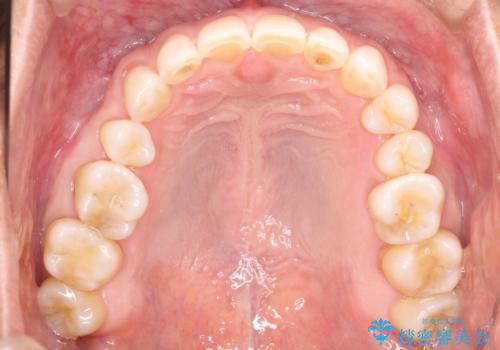

上の前歯の隙間とがたつきをインビザラインできれいな歯並びへ

使用時間を守っていただけたので、比較的スムーズに矯正を終了することができました。

- 7ヶ月